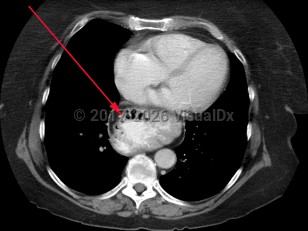

Hiatal hernias are classified as sliding or paraesophageal:

- Type I: sliding hernia – Most common type, due to progressive weakening of the gastroesophageal junction allowing a portion of the gastric cardia to slide upward with increased abdominal pressure, swallowing, and respiration. Patients with type I hernias are more likely to have gastroesophageal reflux disease (GERD).

- Types II, III, IV: paraesophageal hernia – Herniation includes viscera other than the gastric cardia, including gastric fundus and the colon. In type II and III hernias, the stomach becomes "inverted," possibly leading to gastric volvulus.